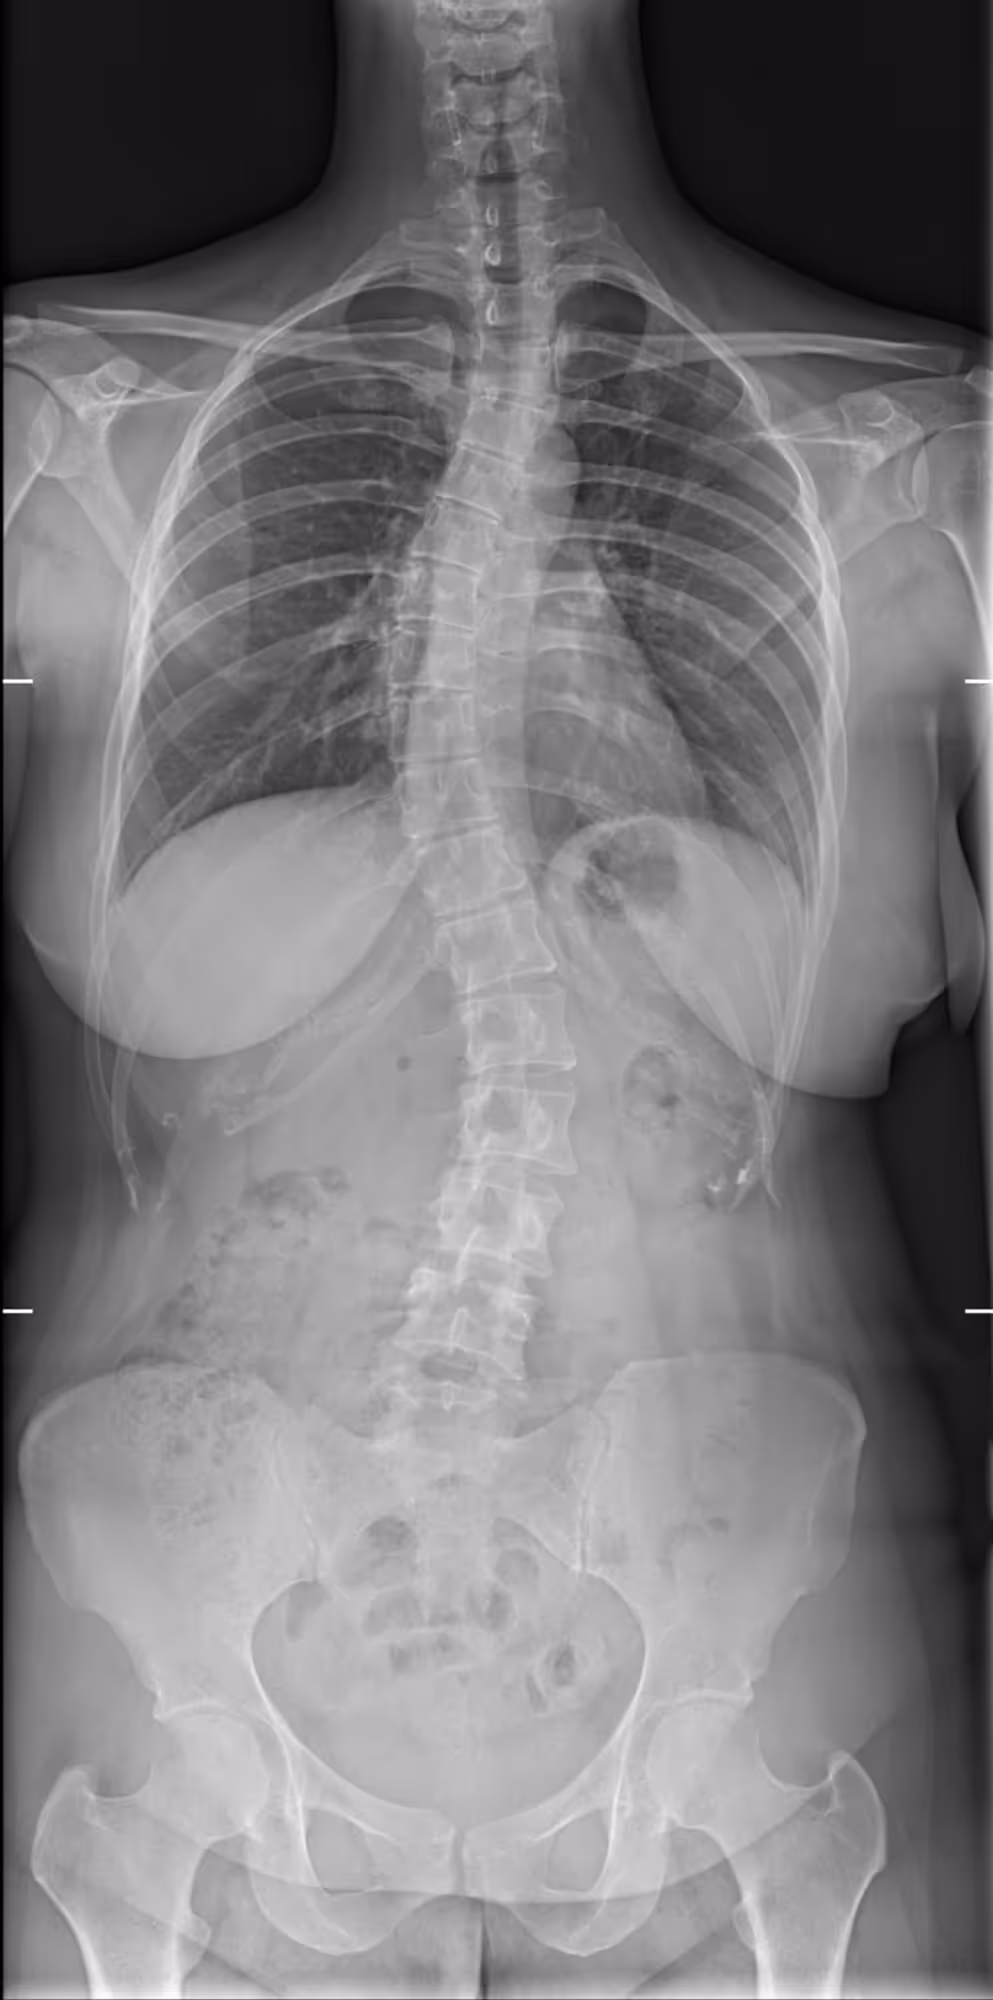

A 30-year-old female presenting with dorsal main, and a history of untreated scoliosis in childhood.

BoneMetrics identified three distinct Cobb angles, consistent with a triple curve scoliosis.